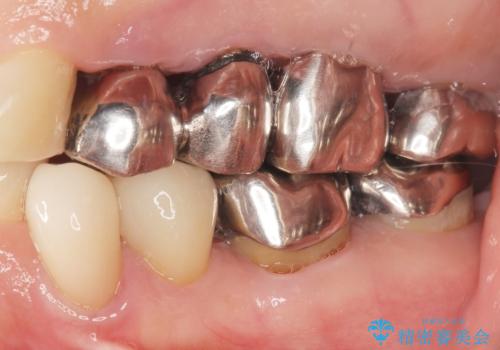

- 虫歯と歯並びを治したいとご希望された患者様です。

精査したところ、左下の小臼歯(左下5)の銀の詰め物の下に大きなう蝕を認めました。

またその手前の歯(左下4)は頬側転位していることを気にされておりました。

矯正をおすすめしましたが希望されず、最小限の方法で虫歯と歯並びを治したいとのことでした。

患者様のご希望により、セラミッククラウンにより可及的にう蝕除去後の補綴及び歯並びの改善を行いました。